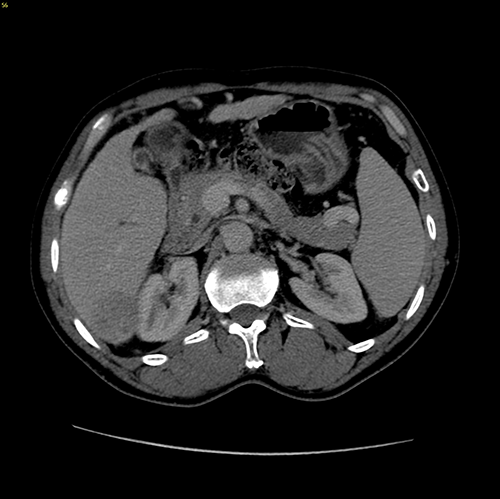

S67肝癌--腹腔镜S67切除